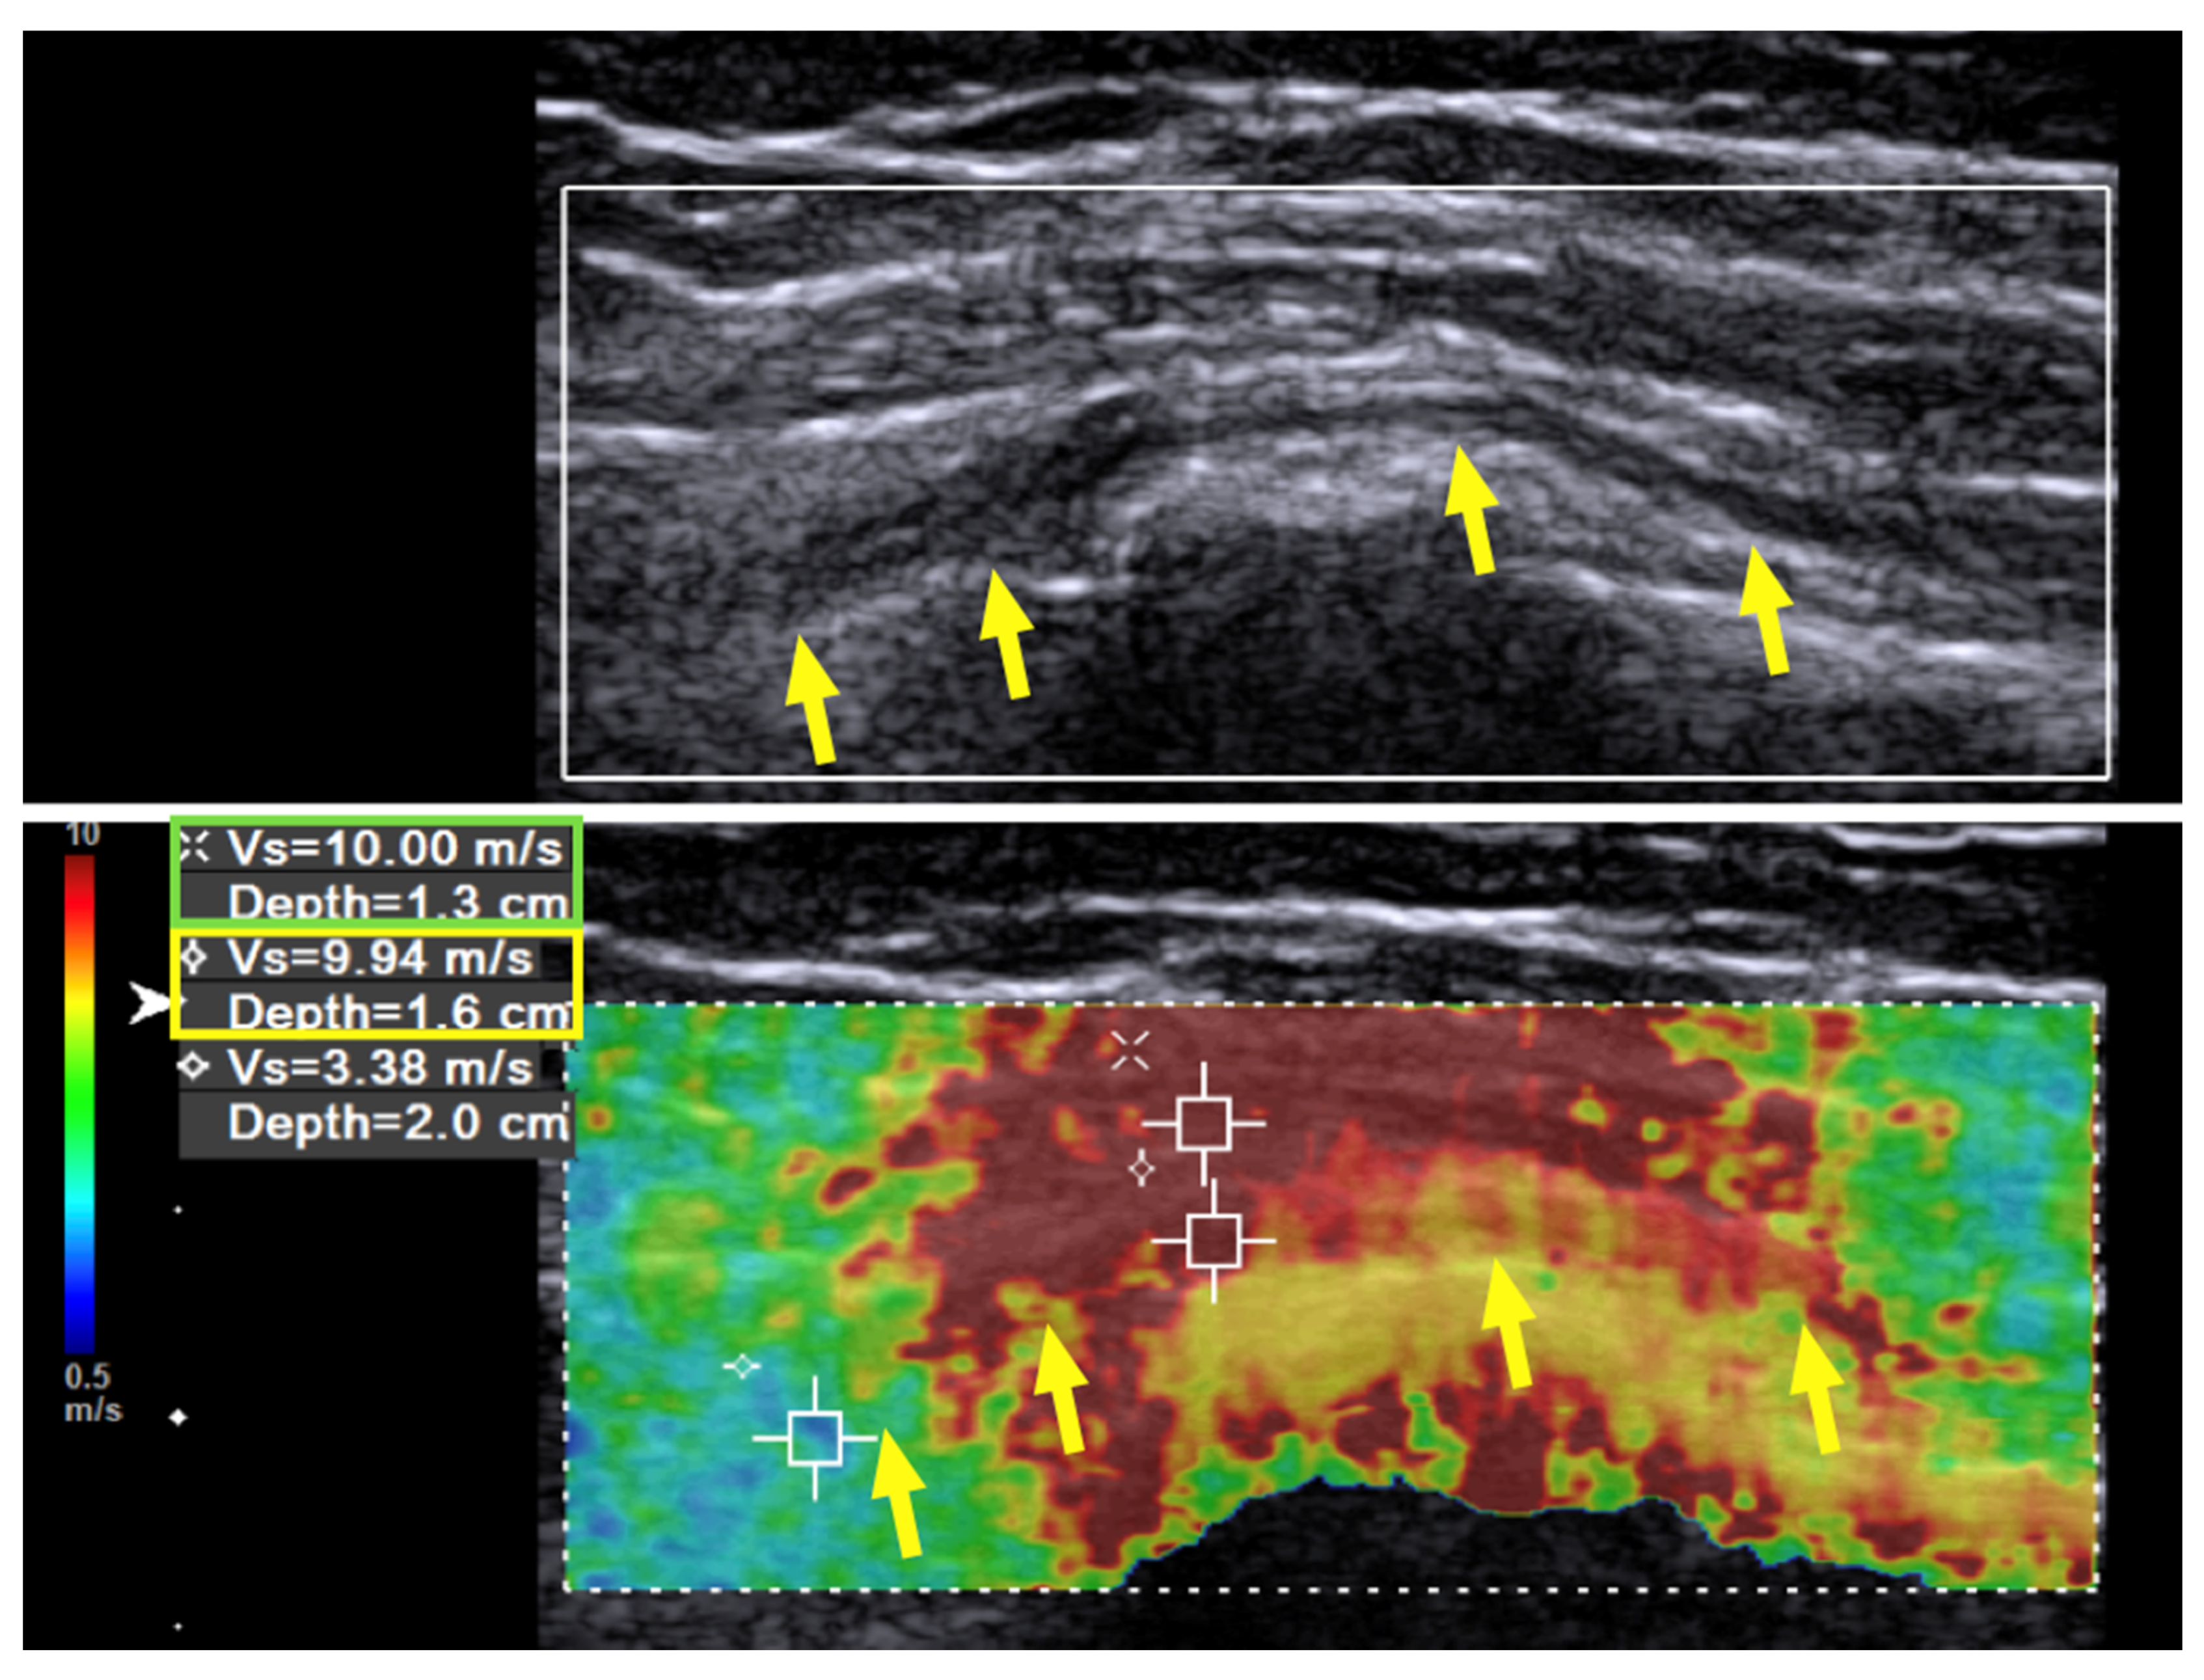

Case 1: A 31-year-old man sustained a left humeral shaft fracture in a traffic accident and underwent fixation with a dynamic compression plate. Fourteen months later, the plate was removed, after which the patient developed a wrist drop of his left hand. Neurodiagnostic studies (i.e., nerve conduction velocity and electromyography) were performed two months after the surgery and showed severe axonal damage with no signals from the radial nerve. Spontaneous activity was noted over the supinator, extensor carpi radialis longus (ECRL), extensor digitorum communis (EDC), and extensor indicis proprius (EIP) muscles, without any motor unit action potentials (MUAP) during recruitment. The ultrasound (US) examination showed a continuous radial nerve with an increased CSA and hypoechoic changes to the nerve fascicles at both the entrance to the spiral groove and supinator levels. Our US system (Acuson S3000, Siemens Healthcare (Pty) Ltd., Erlangen, Germany) entails a linear-array transducer with a bandwidth of 4–9 MHz. The SWV of the radial nerve was assessed using dedicated software (Virtual Touch Tissue Imaging Quantification (VTIQ), Siemens Healthcare (Pty) Ltd., Erlangen, Germany). With the VTIQ software, SWV can be assessed from 0–10 m/s. Segment-by-segment SWE was performed over the course of the radial nerve in the left upper arm, and increased hardness (SWV = 9.94 m/s) was identified at the entrance to the spiral groove, where the nerve starts to wrap around the humerus (Figure 1). The SWV of the contralateral side was 4.05 m/s (Figure 2).

Figure 1. Case 1: Shear wave velocity before hydrodissection. Shear wave velocity (SWV) investigation of the radial nerve over the spiral groove before hydrodissection in a 31-year-old man with wrist drop following plate removal after humerus fracture osteosynthesis. Multiple regions of interest are selected, including the radial nerve and the surrounding tissues. The SWV of the radial nerve is 9.94 m/s and that of the surrounding soft tissue is 10 m/s. Yellow arrow and box: radial nerve in longitudinal view. Green box: scar tissue.